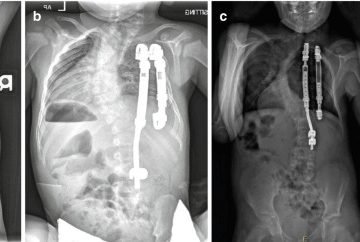

- عکسبرداری (X-ray): معمولاً در حالت ایستاده یا نشسته. با این تصاویر زاویهی انحراف (زاویه کاب که نشاندهندهی درجهی اسکولیوز است) و کجی لگن مشخص میشود.

شایعترین جراحی، فیوژن ستون فقرات از پشت همراه با ابزارگذاری است:

- جراح میلهها و پیچهای مخصوص را به ستون فقرات متصل میکند و از گرافت استخوانی برای اینکه ستون فقرات را در جای خود نگه دارد استفاده میکند.

- فیوژن معمولاً از ستون فقرات پشتی فوقانی تا لگن امتداد مییابد (اغلب به فیوژنهای طولانی نیاز است زیرا کجی لگن شایع است).

- برای ثابت کردن لگن از پیچهای قوی مخصوص استفاده میشود.

- جراحی جلوی پیشرفت انحنا را میگیرد.

- تعادل در نشستن بهبود زیادی پیدا میکند.

- لگن صافتر میشود و نشستن روی ویلچر راحتتر است.